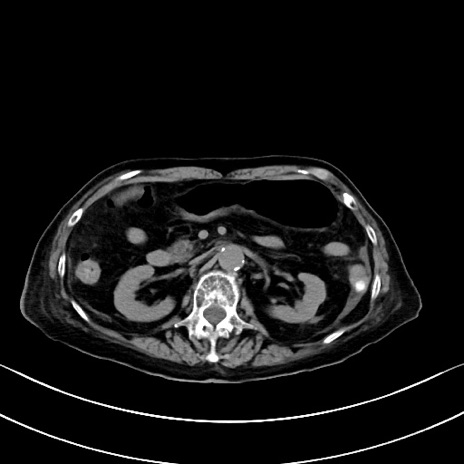

横断像

他院CT